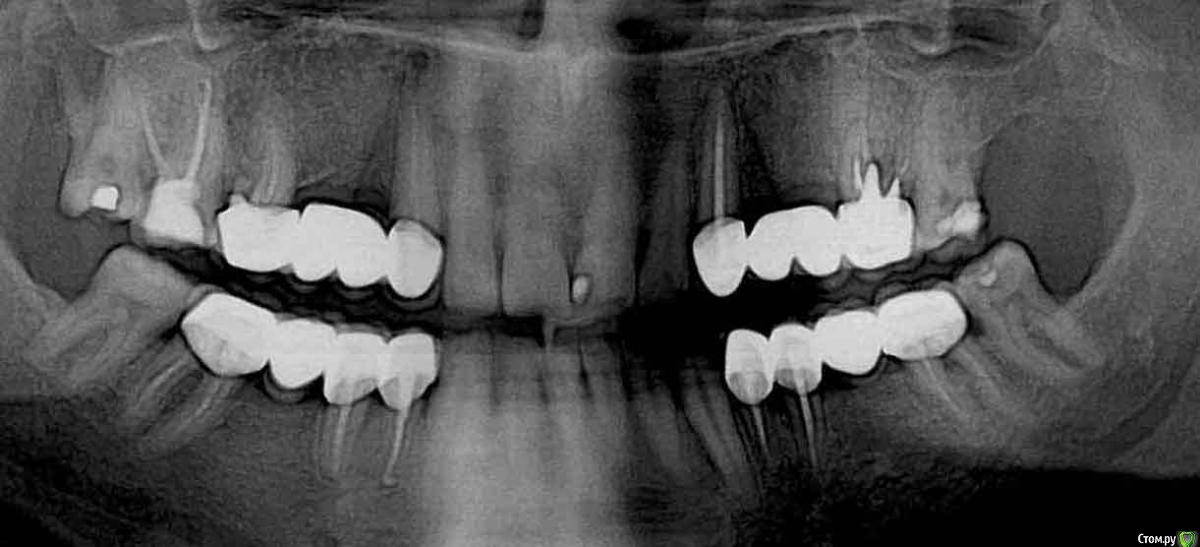

Анестезиолог Опубликовано 27 августа, 2017 Поделиться Опубликовано 27 августа, 2017 Пришло время менять мост на имплантаты (как видите, шестёрка справа сверху никуда, кажется это №16, есть симптоматика периодонтита уже неделю, еле-еле успокоил а/б и Нурофеном).Хирург посмотрел снимок и обратил внимание на стоящие уже. Прокомментировал следующим образом: "Надо было ставить не три импланта, а два, так как из-за того, что они стоят близко - средний и дистальный - нарушено питание костной ткани и она уходит. Кроме того, на названных имплантах слитные коронки, смысла в этом нет, только ухудшает гиг. мероприятия. Я поставлю два ипланта и мост на 3 единицы на них. Коронка на клыке останется временно, потом переставим".Вопросы:1. Правда ли, что есть ошибка в первой имплантации?2. Возможно ли не менять коронку на клыке? Жалоб писать ни на кого не собираюсь, судиться тоже, ответы не выйдут за рамки темы, просто мне для информации и планирования дальнейшей жизни части жевательного аппарата. Панорамные снимки моей улыбки в динамике прилагаю. Ссылка на комментарий

Bier Опубликовано 30 августа, 2017 Поделиться Опубликовано 30 августа, 2017 показаний к удалению 16го не увидел. Скорее всего его можно перелечить, если грамотный врач с микроскопом. А может он и через коронку все вылечит, через микродоступ. Если надо врача посоветую. по имплантатам слева уже все сказали. Если будете имплантаты ставить, и удалять 16й, то лучше 2 имплантата 16,14 и мост. Коронку на клыке можно и не менять, если получится аккуратно отпилить без сколов керамики. Но на боковой поверхности будет металл видел. Ссылка на комментарий

Анестезиолог Опубликовано 30 августа, 2017 Автор Поделиться Опубликовано 30 августа, 2017 Спасибо. Перелечивали уже, и с микроскопом тоже. И мост меняли. Так и планируется 16-14 и мост на них. Ссылка на комментарий